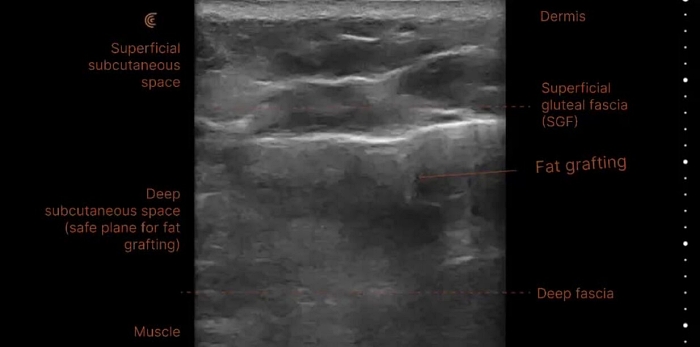

1.施打層次:打對位置比打得多更重要

皮膚看起來薄薄一層,但實際上解剖結構可分為 表皮、真皮、淺層脂肪、SMAS筋膜、深層脂肪、韌帶與骨膜等,不同的材質、不同的目的(如填平 vs 撐提),必須注射在正確的層次。施打的層次錯誤是造成動態表情不自然、笑起來像「一塊肉」卡住的主要饅化原因。

臨床重點:越動的部位,越不該填在淺層,例如眼下,容易出現「丁達爾效應」在光線下呈現藍灰色。此外,硬度較高的玻尿酸打在皮下脂肪的淺層,填充物會直接跟著肌肉運動而位移,導致擠壓、堆疊、出現塊狀感。

過去醫師只能憑肉眼、觸診與經驗來猜測填充物的位置與狀況,不清楚是玻尿酸、脂肪、還是其他材質,也無法區分是哪一層結構,饅化修復容易變成「瞎修」。現在,高解析度超音波已成為饅化修復的「導航圖」,可以清楚地看到填充物的層次、範圍與密度,辨識出皮下組織是否有莢膜、纖維化或鈣化。

| 深度層次定位 | 精準分層 | 確認填充物位於真皮層、皮下脂肪層、筋膜層或骨膜層等,有利後續處置。 |

自體脂肪填充

自體脂肪是許多人認為最「天然」的選項,但也可能帶來最難處理的饅化結果之一。當注射量過多、分佈不均或細胞存活率不佳時,壞死的脂肪會被人體吸收、纖維化,最後形成硬塊或疤痕結節。在超音波影像下,這些脂肪殘留或纖維化區塊呈現為亮白片狀的高回音區域,邊界模糊、與周圍組織混合,難以單獨區分。

患者常反應觸感不均、面部不對稱,甚至有下垂與拉扯感。處理方式與膠原增生劑類似,但更需要分層細緻鬆解+體積微調。某些案例還須搭配抽脂做空間釋放,使臉部恢復原有線條的流動性與自然感。